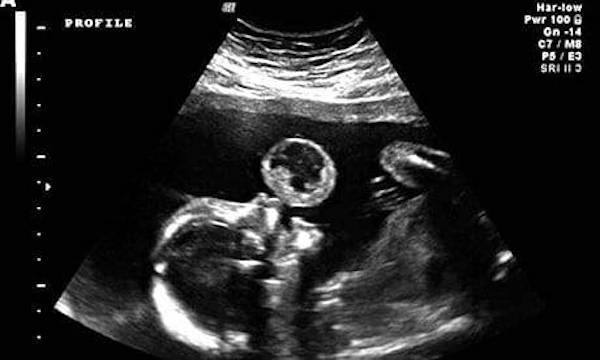

Tammy Gonzalez era una mamma come tante che, un giorno, osservando l’ecografia della figlia ancora in grembo alla 17° settimana di gravidanza, ha notato quella che sembrava un’enorme palla sopra la bocca della piccola. La mamma pensava che la piccola stesse facendo una bolla con il liquido amniotico, ma il medico invece è rimasto in silenzio per 5 minuti. Il responso è stato terribile: la figlia di Tammy aveva un tumore fetale. Si trattava di un tumore molto raro: un teratoma. C’è solo 1 probabilità su 100 mila che si verifichi.

Ad effettuare la pionieristica operazione sono stati i chirurghi dell’University of Miami/Jackson Memorial Hospital, per la precisione Gonzales e sua moglie Eftichia Kontopoulos. La coppia ha usato un endoscopio guidato dagli ultrasuoni. Usando un lases hanno eliminato la massa tumorale nella sua bocca.